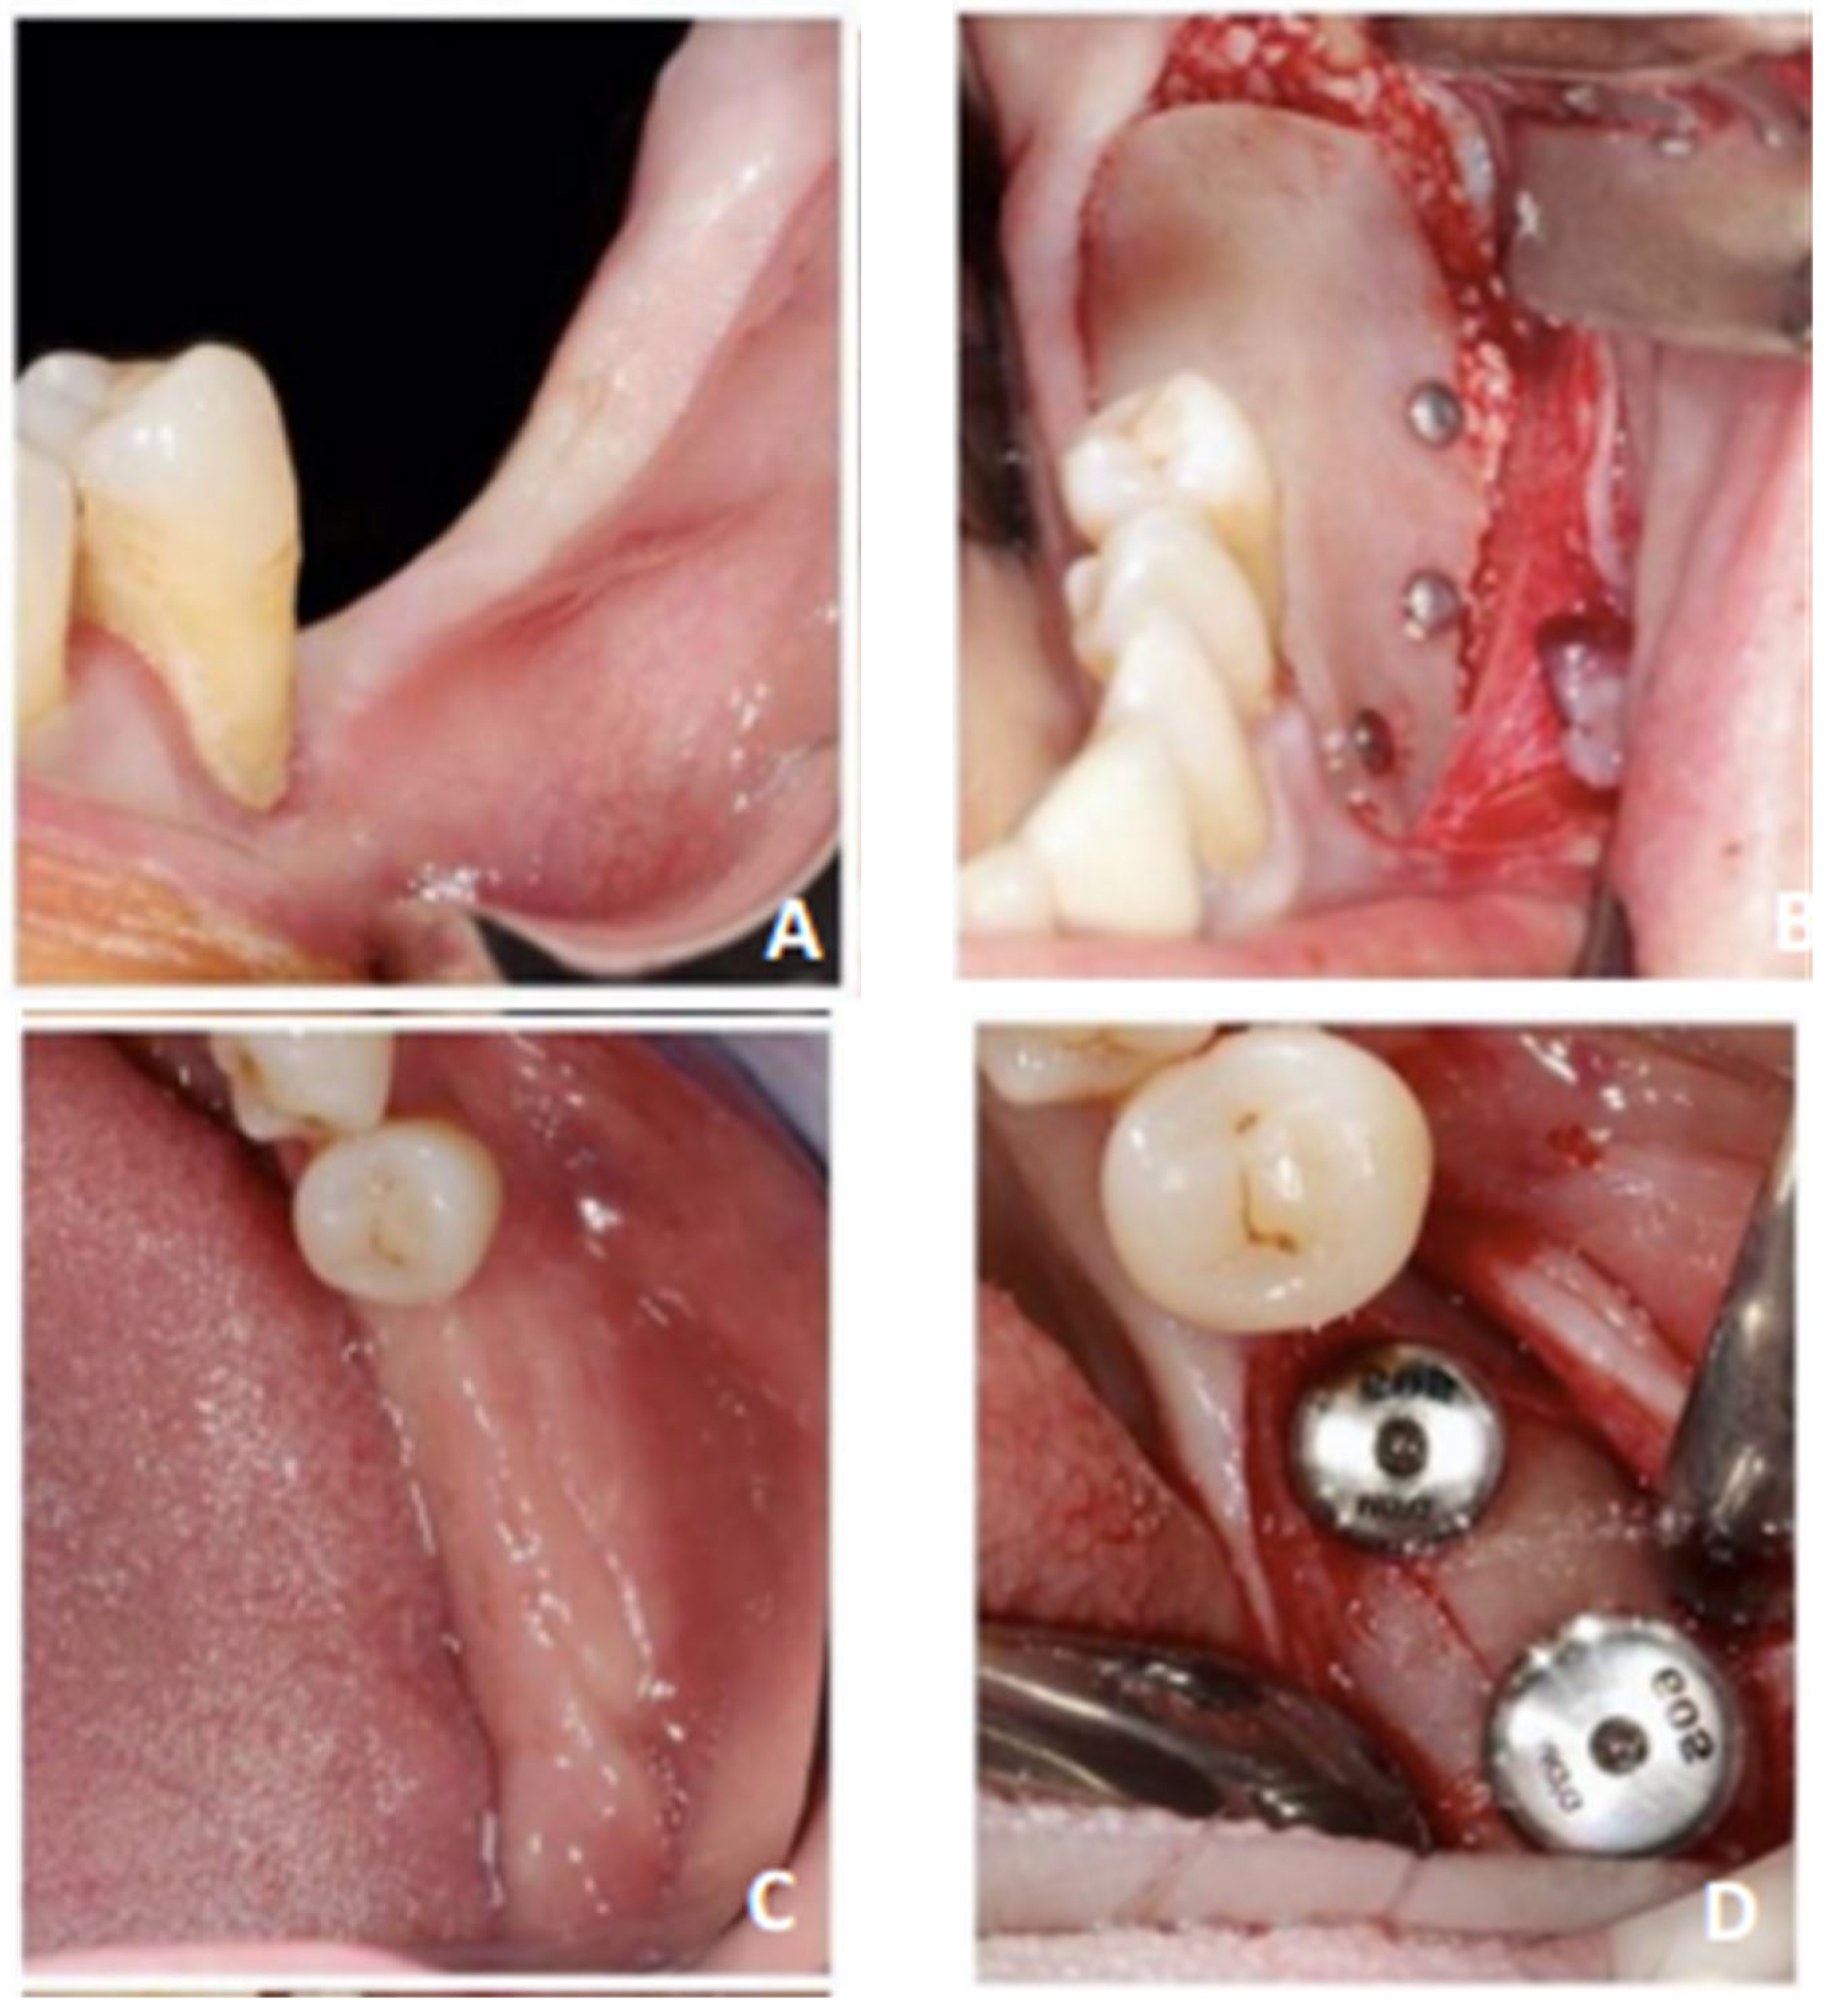

2. Materials and Methods

3. Results